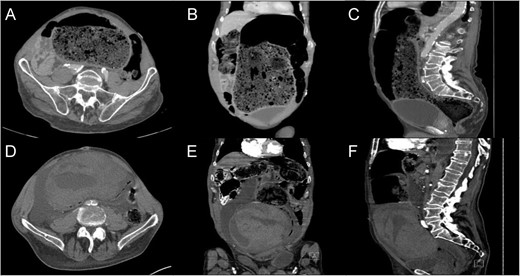

CT – Abdomen and Pelvis with intravenous contrast. Admission imaging demonstrating large colonic stool burden in the axial (A), coronal (B) and sagittal orientation (C). CT abdomen and pelvis following enema demonstrating large colonic wall hematoma axial (D), coronal (E) and sagittal orientation (F).